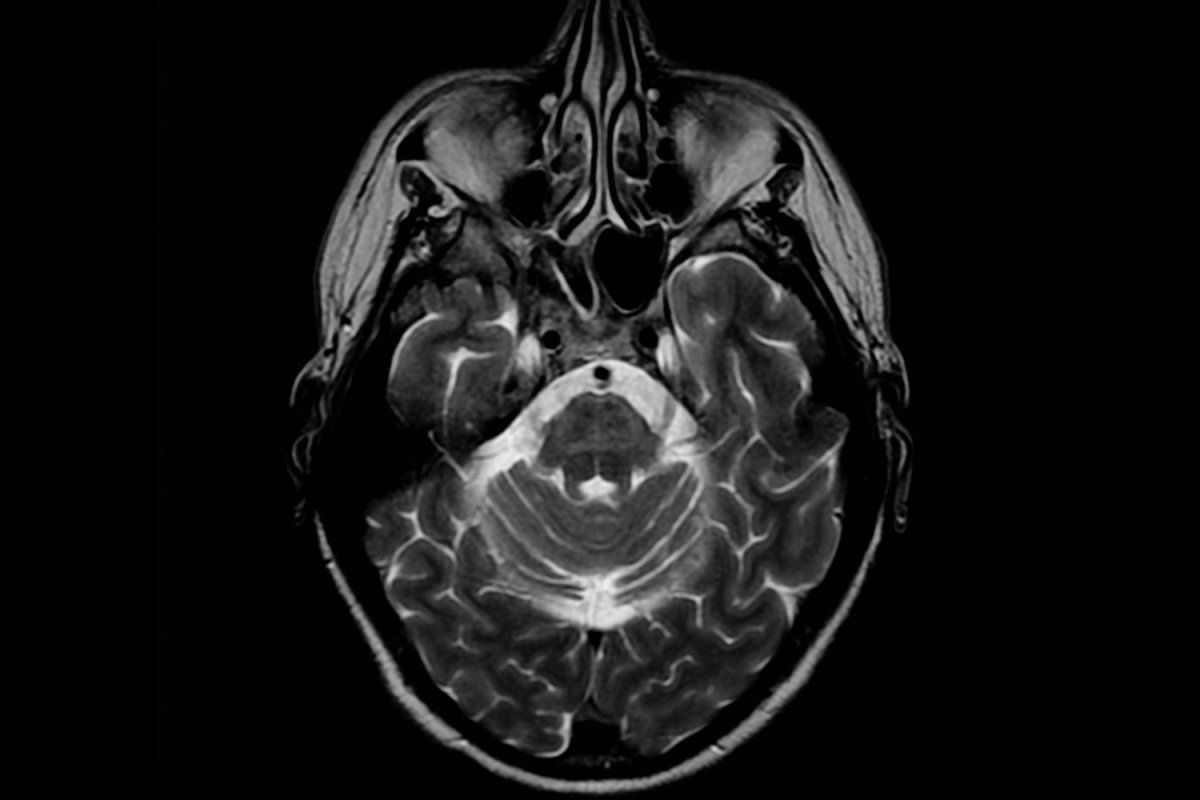

NEW PRION: Teams led by Nobel laureate Stanley Prusiner, MD, and and Kurt Giles, DPhil, discovered a new type of prion that causes Multiple System Atrophy (MSA), a neurodegenerative disorder with similarities to Parkinson’s disease. It’s the first discovery of a human disease caused by a new prion in 50 years, since work at the National Institutes of Health showed that human brain tissue infected with Creutzfeldt-Jakob Disease could transmit neurodegeneration to chimpanzees. Image courtesy of A.Prof Frank Gaillard, Radiopaedia.org